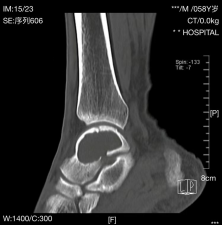

术前CT检查

后廖先生经朋友介绍来到我院关节与运动医学科就诊,在完善踝关节CT和核磁共振(MRI)检查后,主任医师王小勇迅速找到了患者的病因:距骨骨囊肿(巨大)。鉴于囊肿巨大,保守治疗效果差,存在骨折风险,遂建议患者手术治疗。由于正常骨被病损所占据,造成骨缺损,大大降低了骨骼的坚固性。因此,手术治疗的目的是彻底清除病灶,消灭囊腔,防止病理性骨折及畸形的发生,恢复骨的坚固性。